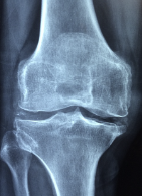

뼈 관절에 좋은 음식 및 뼈 관절에 관한 정보에 대해 알아보도록 하겠습니다. 뼈 관절은 뼈를 서로 연결하여 움직임을 가능하게 하는 부위를 말합니다. 뼈 관절은 인체의 운동 기능을 수행하는 중요한 역할을 하며, 뼈와 뼈, 뼈와 근육, 뼈와 연골 등 다양한 부위에서 발생합니다. 뼈 관절은 크게 공동강, 일반강, 역삼각형, 공동강, 원형관절 등의 형태로 나누어집니다.뼈 관절은 움직이는 부위이기 때문에 과도한 운동이나 부상, 노화 등으로 인해 손상될 수 있습니다. 뼈 관절에 생기는 문제로는 골관절염, 류마티스 관절염, 슬관절염 등이 있으며, 이러한 질환은 통증, 염증, 운동 제한 등의 증상을 유발할 수 있습니다.

4. 슬관절염: 슬관절염은 무릎 관절의 손상 및 염증으로 인한 통증을 보입니다.